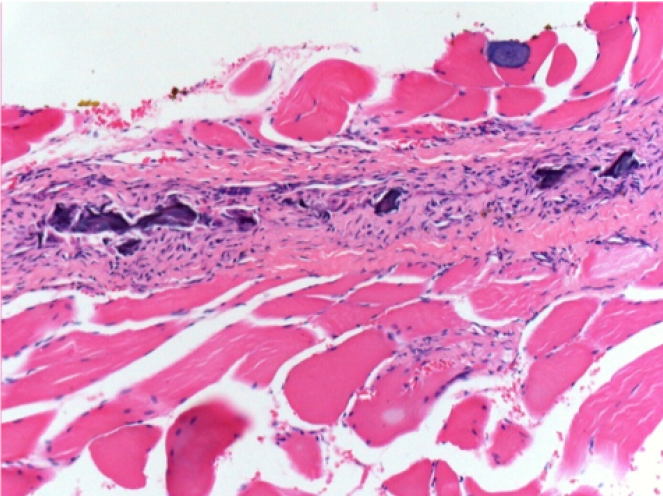

1 month after Endopeel Injection 0.1ml in the right pretibial muscle.

What is seen in black on the pictures is not a necrosis like could imagine some scientifics !

In fact, 4 conclusions have to be taken in consideration